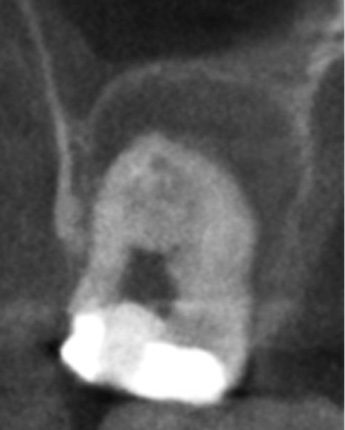

かぶせ物が不適であること(青矢印部)、近心根に根尖病巣があること(青枠部)、根充剤がかなり太いため(赤矢印部)歯質が薄くなっていることなど問題点がいくつかありましたが、他院で治療をしたばかりであり、また上記の条件から再治療には抜歯のリスクが非常に高いことから初診時は患者さんと相談し経過観察することになりました。